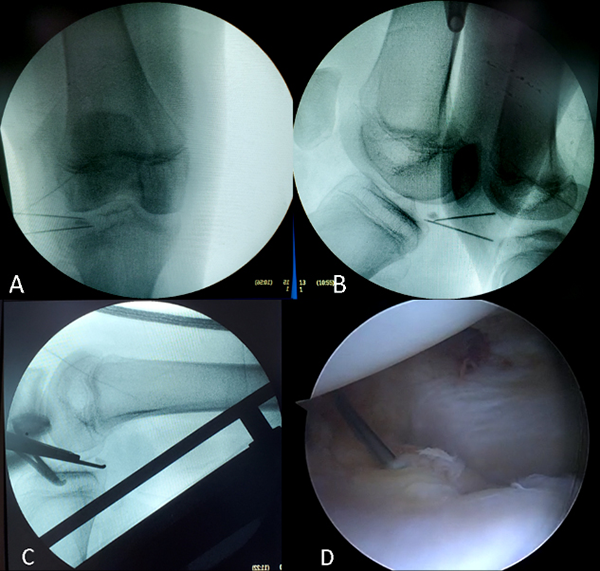

Luego de una búsqueda exhaustiva, al no visualizarse el segundo fragmento, se utilizó el intensificador de imagen intraoperatorio que ubicó este cuerpo extraño en la región posterior y lateral del compartimento lateral (figs. 6A y 6B). Por visión radioscópica y artroscópica simultánea no se había conseguido visualizar el fragmento (fig. 6C), pero artroscópicamente se logró palparlo en forma percutánea con una aguja: se localizó a nivel del ojal del poplíteo, incluido en el espesor de la sinovial y ligamento meniscofemoral (fig. 6D).

Se realizaron dos portales laterales accesorios (fig. 7A), se efectuó la apertura sinovial (fig. 7B), e identificó el fragmento por debajo y posterior del cuerno posterior del menisco externo. Se procedió a una apertura longitudinal del ligamento meniscofemoral posterior, empujando el tejido con un palpador desde el portal anteromedial (fig. 7C) y a través de uno de los portales laterales se realizó la exéresis del segundo fragmento de 8 mm (fig. 7D). Así, fueron removidos los dos fragmentos de vidrio (fig. 8).

Figura 6. A y B: Visión por intensificador de imágenes, cuerpo extraño en la región posterior y lateral del compartimento lateral. C: Visión artroscópica y radioscópica simultánea. D: Visión artroscópica, palpación del vidrio intratisular.